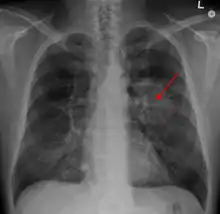

A chest X-ray showing a tumor in the lung (marked by arrow)